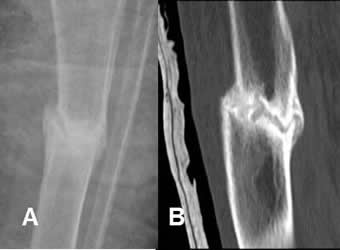

Fig 126. Seudoartrosis.

A: Rx AP. Fractura conminuta de la cabeza humeral.

B: Rx AP. Después de 7 meses persiste separación entre los fragmentos y no se encuentra callo óseo.

C: RM coronal en T2. El espacio entre los fragmentos está ocupado por líquido, confirmando el diagnóstico de seudoartrosis.